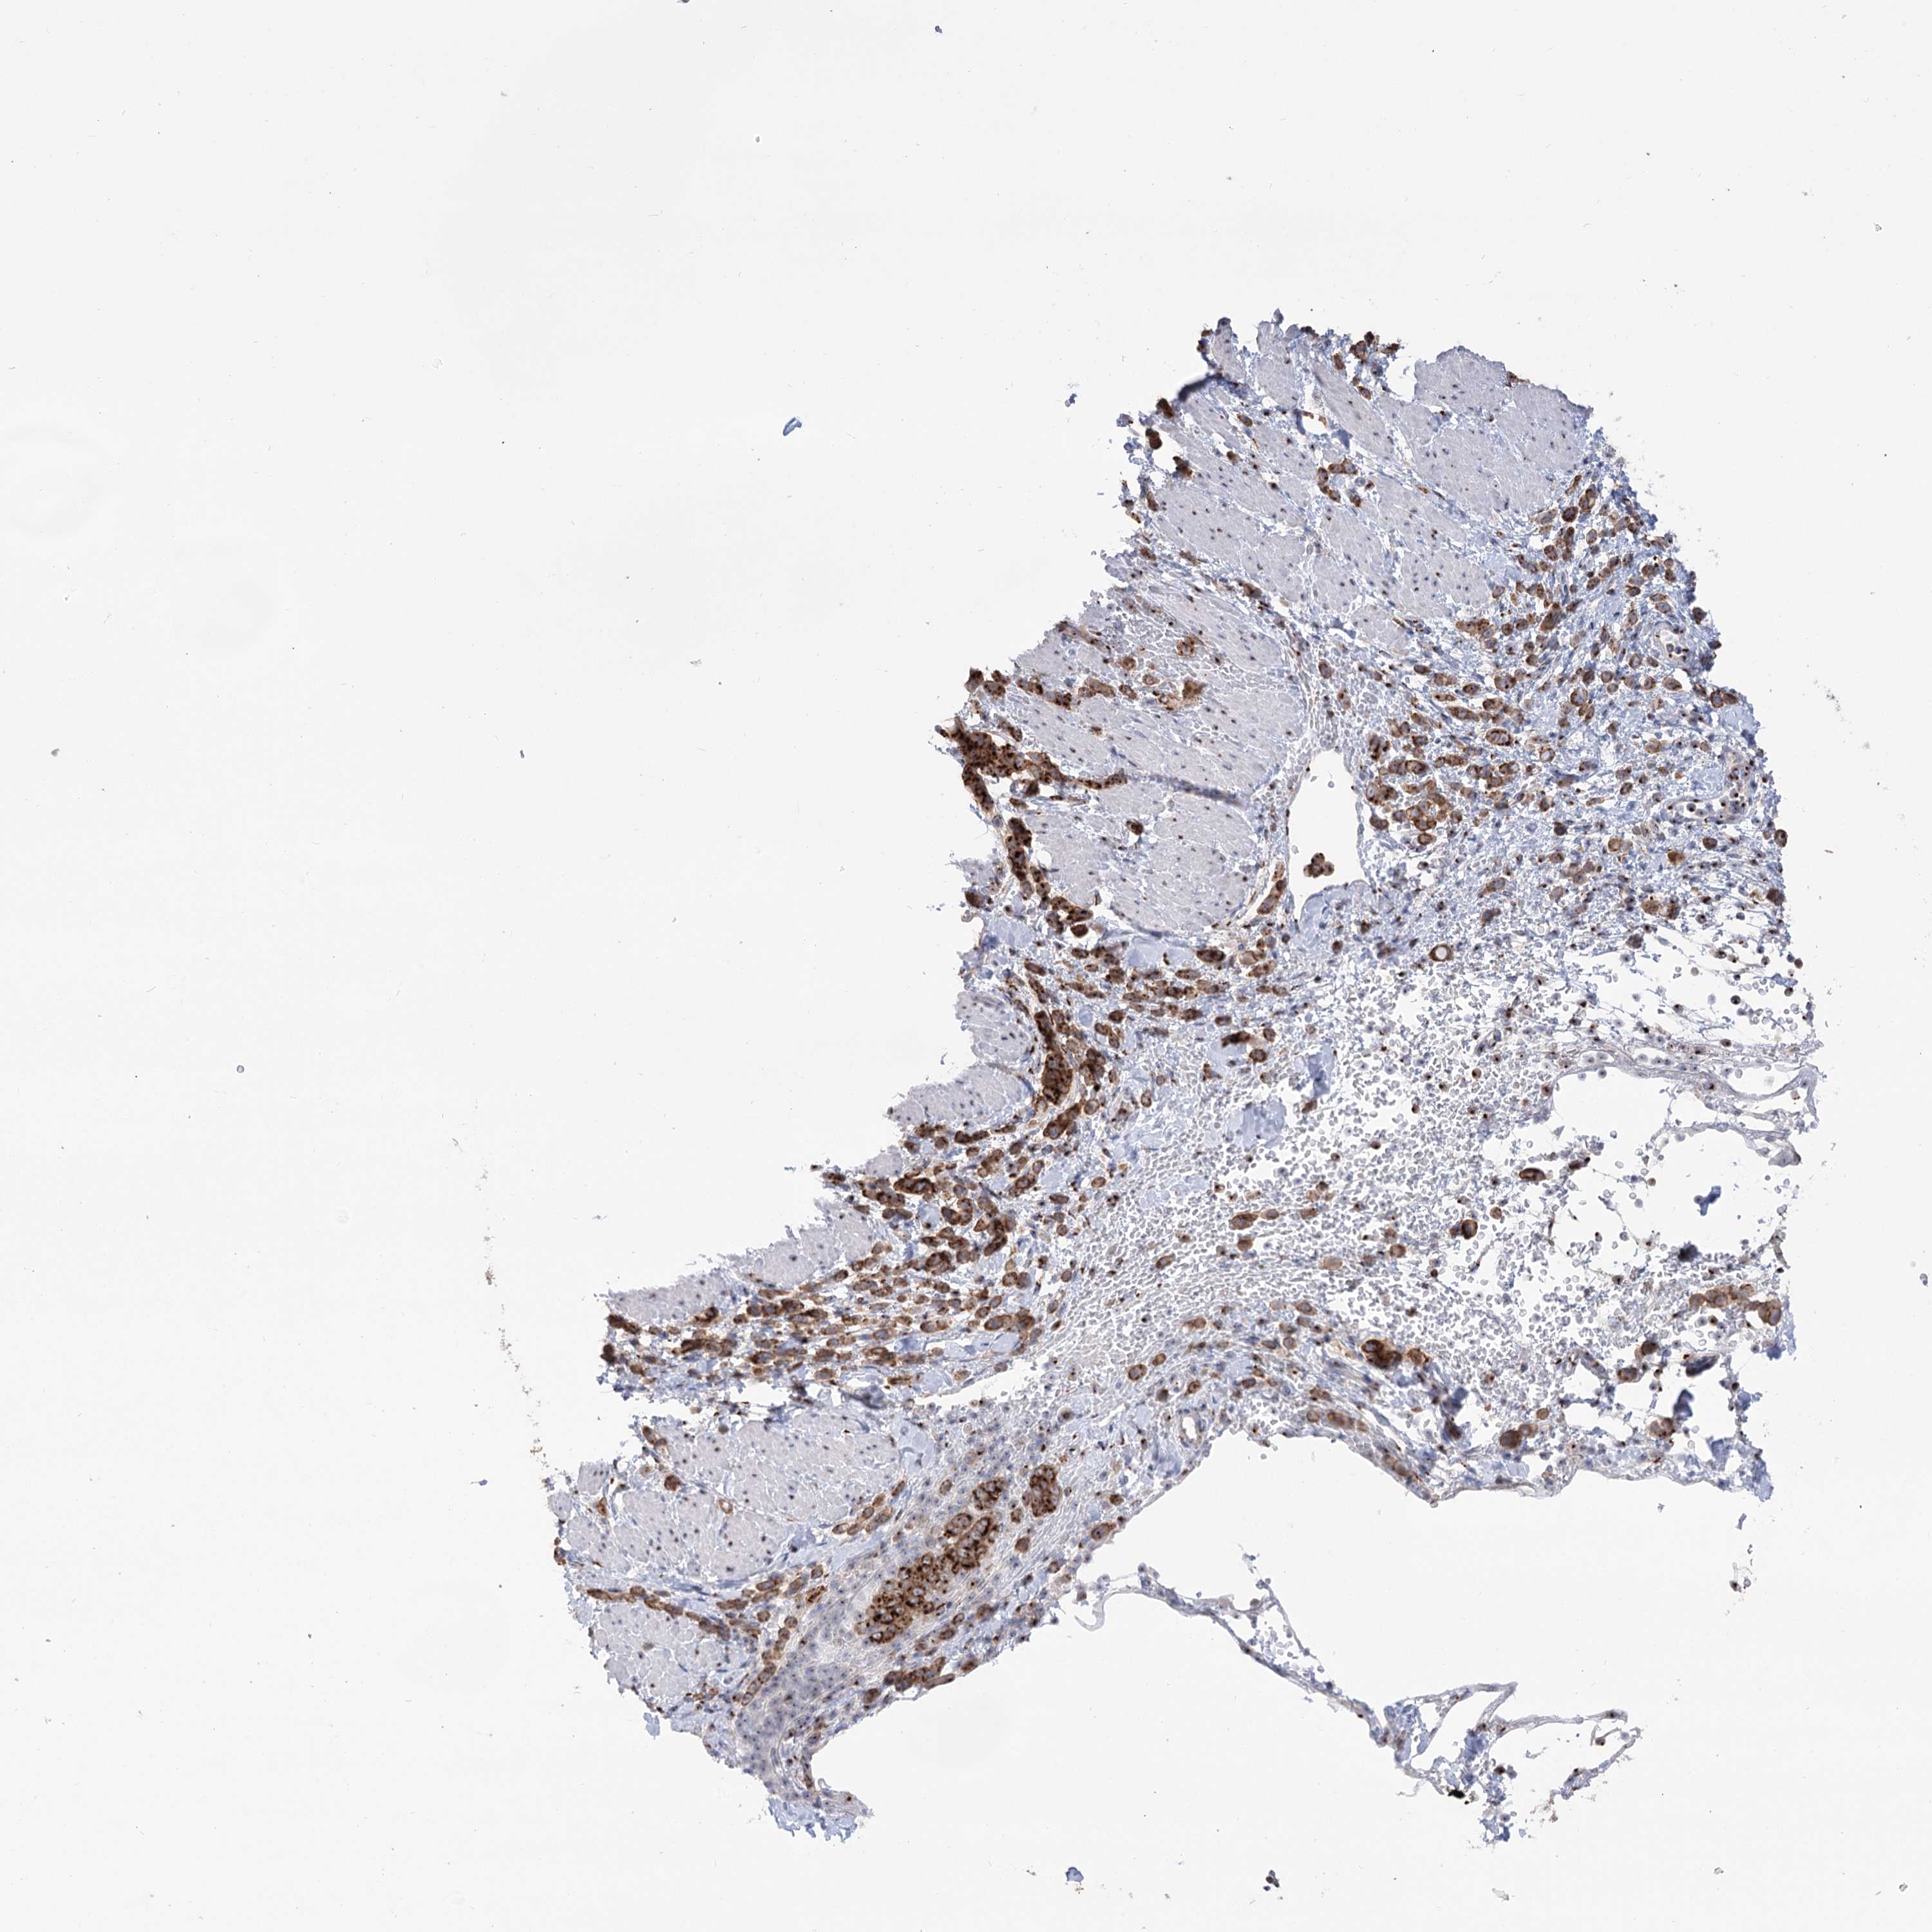

PANCREATIC CANCER - Protein expressioni

A mouse-over function shows sample information and annotation data. Click on an image to view it in a full screen mode. Samples can be filtered based on level of antibody staining by selecting one or several of the following categories: high, medium, low and not detected. The assay and annotation is described here.

Note that samples used for immunohistochemistry by the Human Protein Atlas do not correspond to samples in the TCGA dataset.

Antibody stainingi

Antibody staining in the annotated cell types in the current human tissue is reported as not detected, low, medium, or high, based on conventional immunohistochemistry profiling in selected tissues. This score is based on the combination of the staining intensity and fraction of stained cells.

Each image is clickable and will lead to virtual microscopy that enables deeper exploration of all samples and also displays staining intensity scores, fraction scores and subcellular localization as well as patient and tissue information for each sample.

Antibody HPA038299

Staining

High

Medium

Low

Not detected

Intensity

Strong

Moderate

Weak

Negative

Quantity

>75%

75%-25%

<25%

None

Location

Nuclear

Cytoplasmic/membranous

Cytoplasmic/membranous,nuclear

Adenocarcinoma, NOS